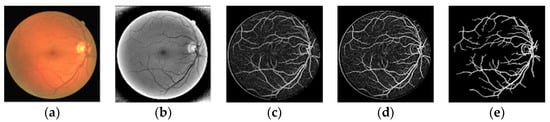

Figure 2.

Multiscale joint Optimization strategy. (a) Original color image; (b) Pre-processing result; (c) Multi-scale filtering; (d) OTSU image segmentation based on PSO (OTSU-PSO); (e) Post-processing.